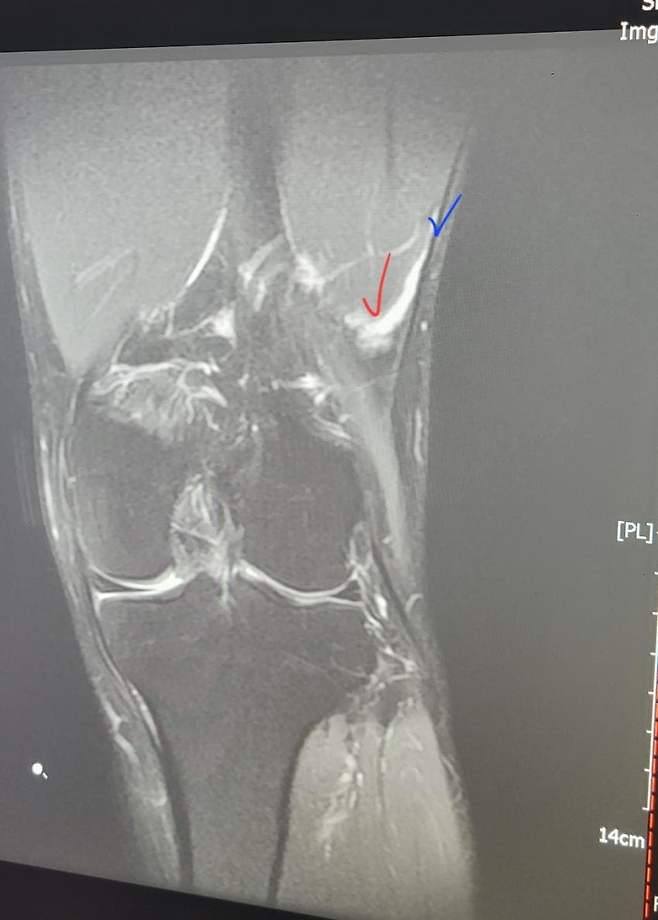

사진에 파란색으로 표시한 검정색 얇은 띠가 장경인대, 빨간표시가 바로 옆에 붙어있는 외측광근에 하얀 염증이 보임.